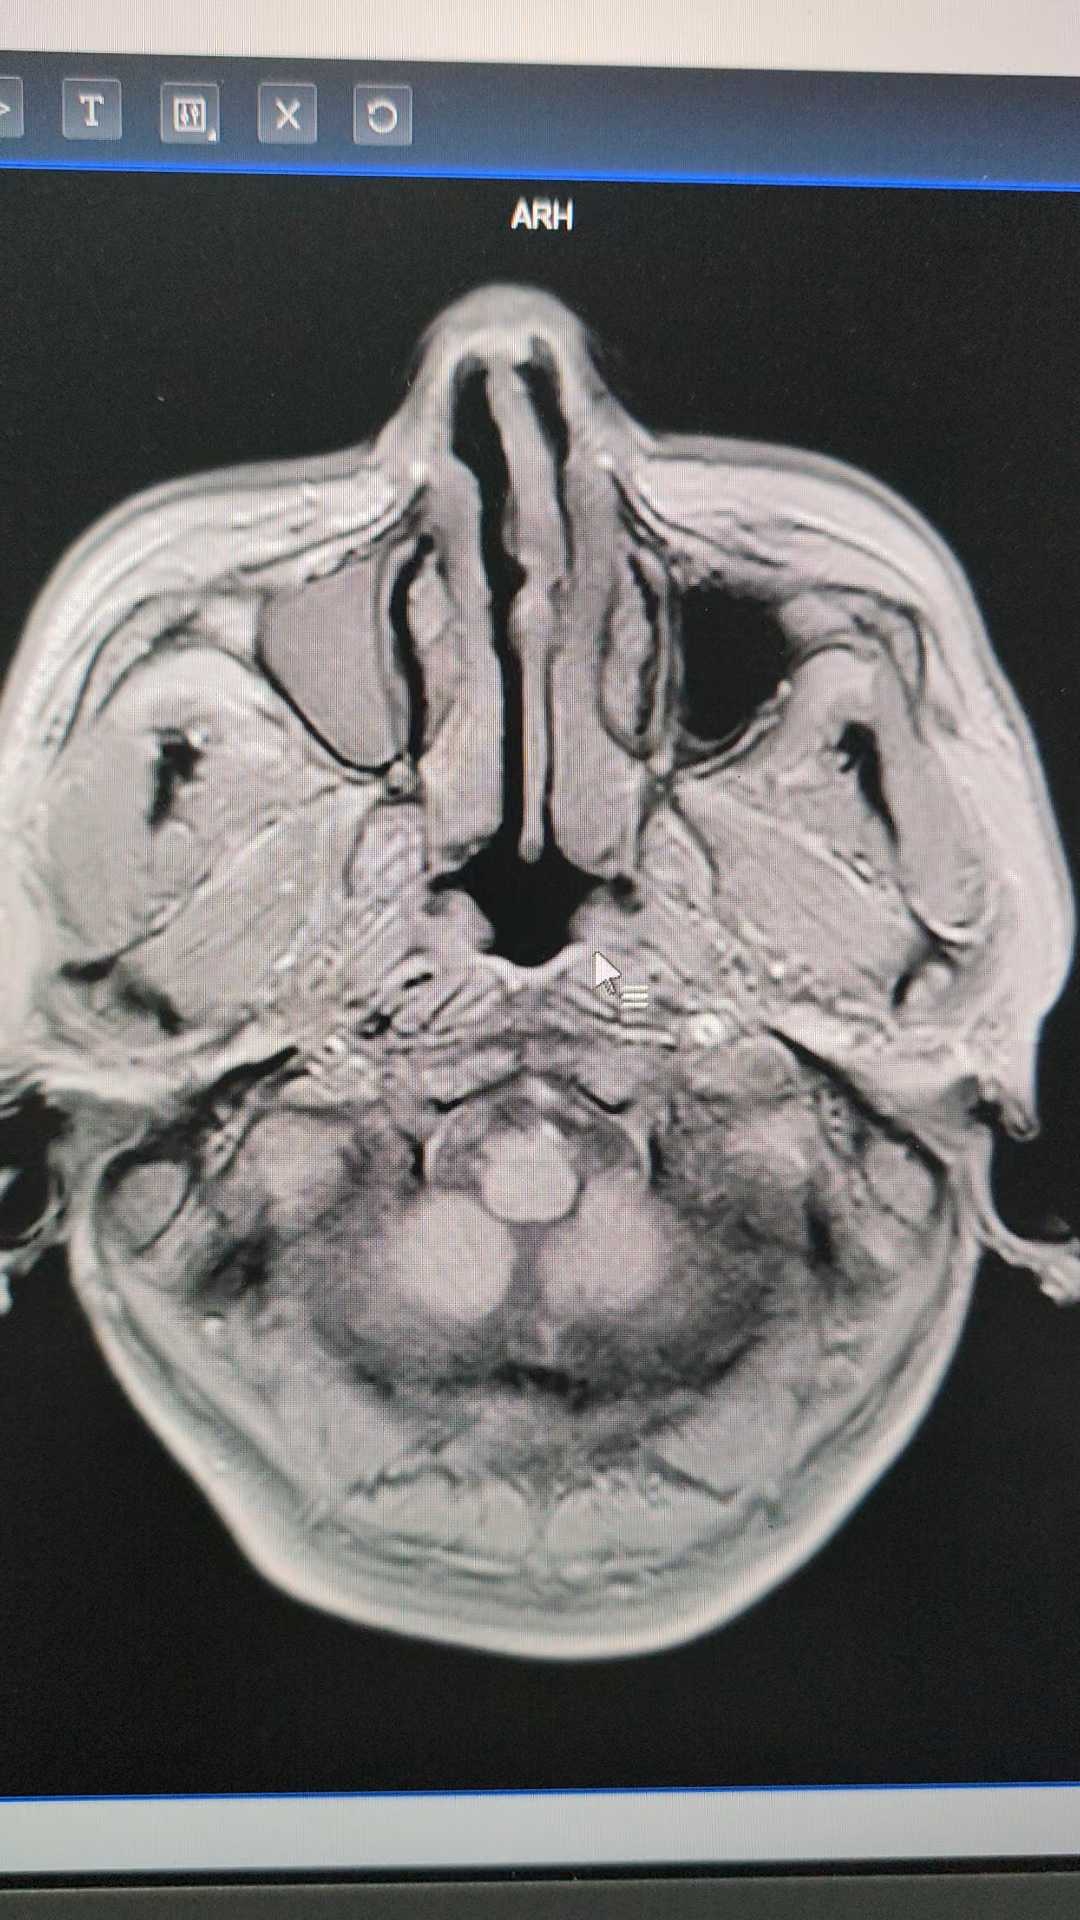

病例疑难:颅内多发病变

患者57岁,2天前因左上肢远端突发乏力体检发现颅内多发病变,目前患者无特殊不适。